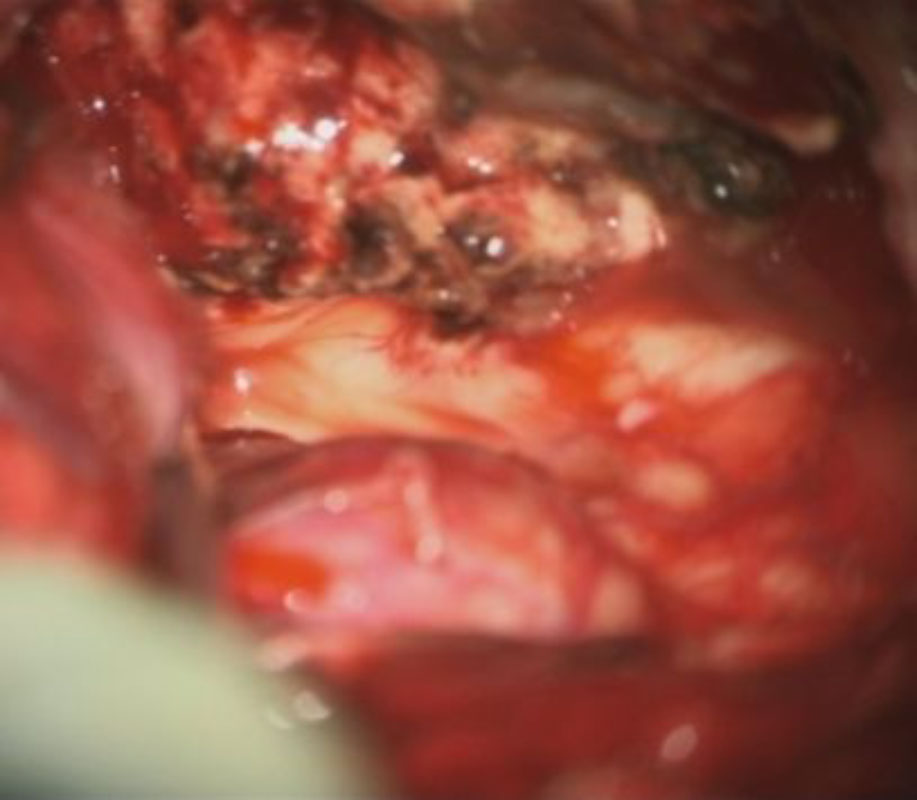

術中写真

摘出 前

摘出 後